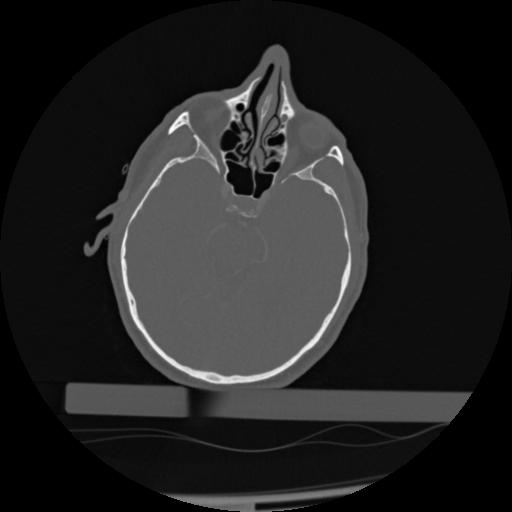

22 ANGIO,CE,Vol,0.5,ANGIO,,